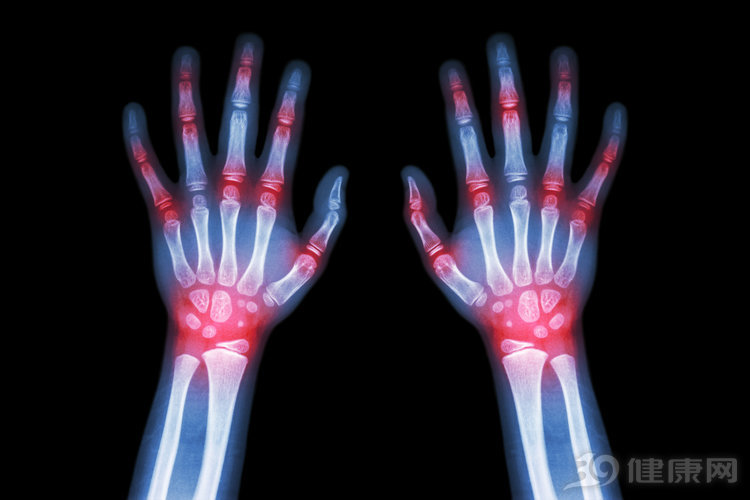

这是一种以关节炎为主要表现的慢性全身性疾病,对关节破坏很大,如不及时治疗,会导致关节畸形、功能受损。由于病情时好时坏,反复发作,治疗难度大,类风湿关节炎在许多病人眼里是“不死的癌症。

有效阻止关节破坏,关键在于早期诊断和规范治疗。该病主要侵犯小关节,当出现多关节的肿痛,尤其是手指、手腕出现肿痛,一定要警惕类风湿关节炎。

规范治疗则抓住类风湿关节炎起病的三个月内,这是国际公认的最佳治疗时机。不仅强调使用控制症状的药物,更要重视使用缓解病的抗风湿药。